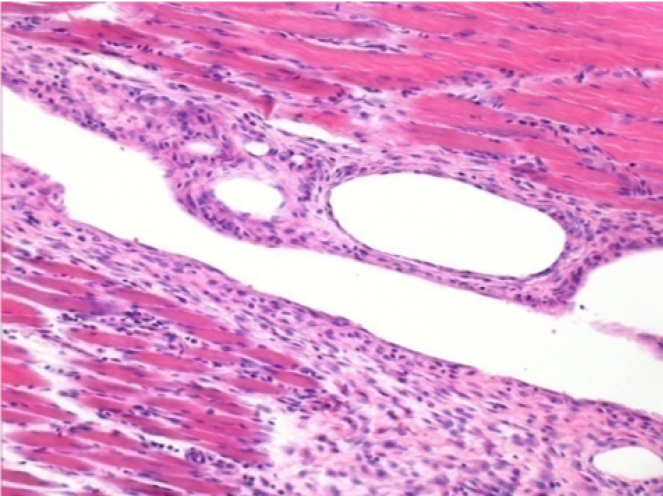

10 giorni dopo iniezione di Endopeel

Scatola Nr 2

- 10 giorni dopo iniezione 0.1ml di Endopeel nel muscolo pretibiale destro (Dx).

- Si osserva formazioni di vacuole , le quali circondate da linfociti.

- Le quali Vacuole sono differenti dal tessuto necrotico.

- La presenza di linfociti é correlata alla permeabilità delle membrane cellulari.

Sx : Controllo-100x-Giorno10

Dx:100x-Giorno10

Dx :200x-Giorno10

Dx :400x - Giorno10